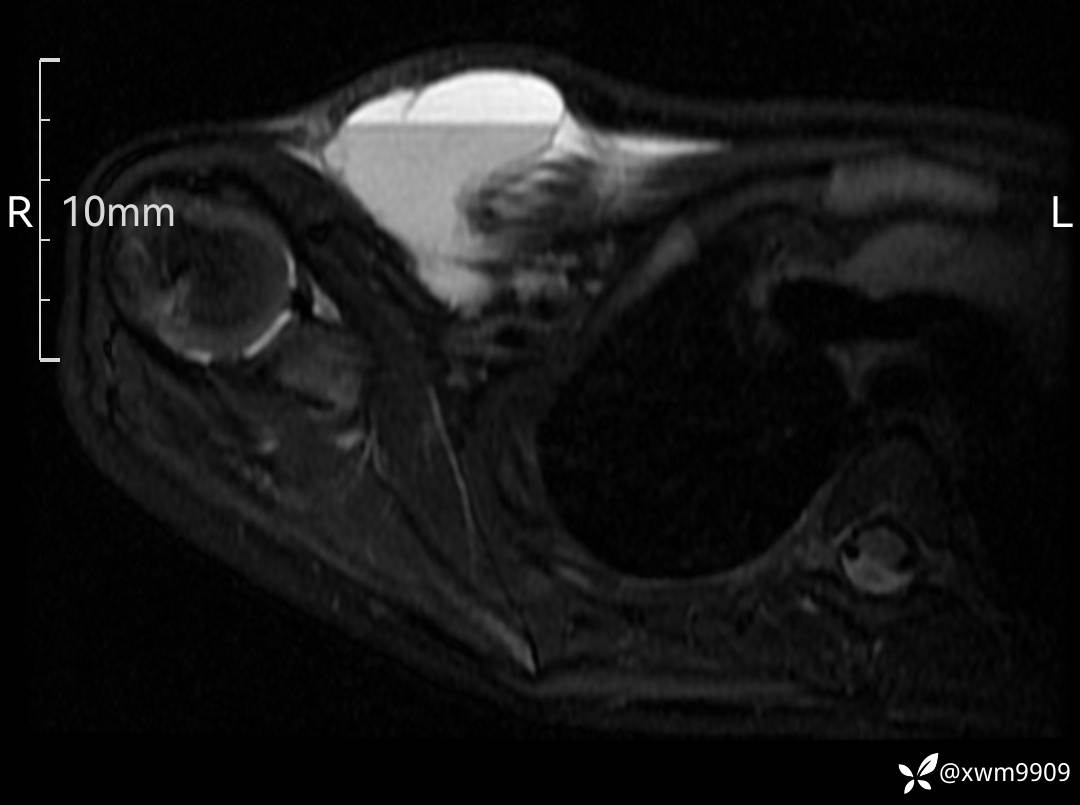

3、查体,右锁下方可及一约5x6Cm肿物,软丶边清丶未见明显发红,肤温不高,压痛明显,不可推动,稍有波动感。其他无特殊。

2、CT、MR肿块内可见液-液平面,常见有哪些疾病。